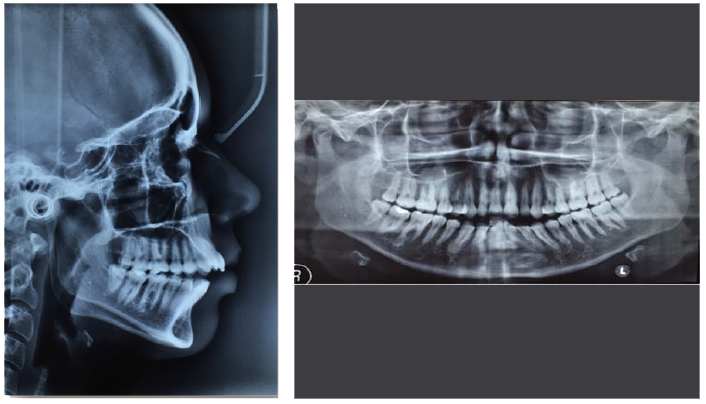

Figure 2 Pre-treatment lateral cephalogram and panoramic radiographs.

Upon completion of clinical examination and review of pretreatment panoramic and lateral cephalogram radiographs the patient was treatment planned with a two phase approach which included a maxillary expansion appliance (phase 1) followed by orthodontic treatment (phase 2) and advised of the potentially favorable prognosis of a new non-extraction orthodontic treatment. She decided to pursue attempted maxillary expansion followed by non-surgical, non-extraction orthodontic treatment in order to correct her bilateral molar crossbite, obtain proper overjet and overbite relations, level and align her occlusion and restore satisfactory esthetics by utilizing the bracket technology system of Fastbraces® (Figure 2).

Clinical results along with photographs and radiographs comparing pre and post treatment show dramatic esthetic and functional improvement, elimination of the bilateral posterior crossbite and correction of anterior guidance with a stable occlusion. Overjet and overbite was measured at between 1 to 2mm with a treatment time of a little over 12months (Figures 3&4). In addition, comparing pre with post treatment cephalograms shows radiographic evidence of an increased upper airway dimension.

Figure 4 Post-treatment lateral cephalogram and panoramic radiographs.